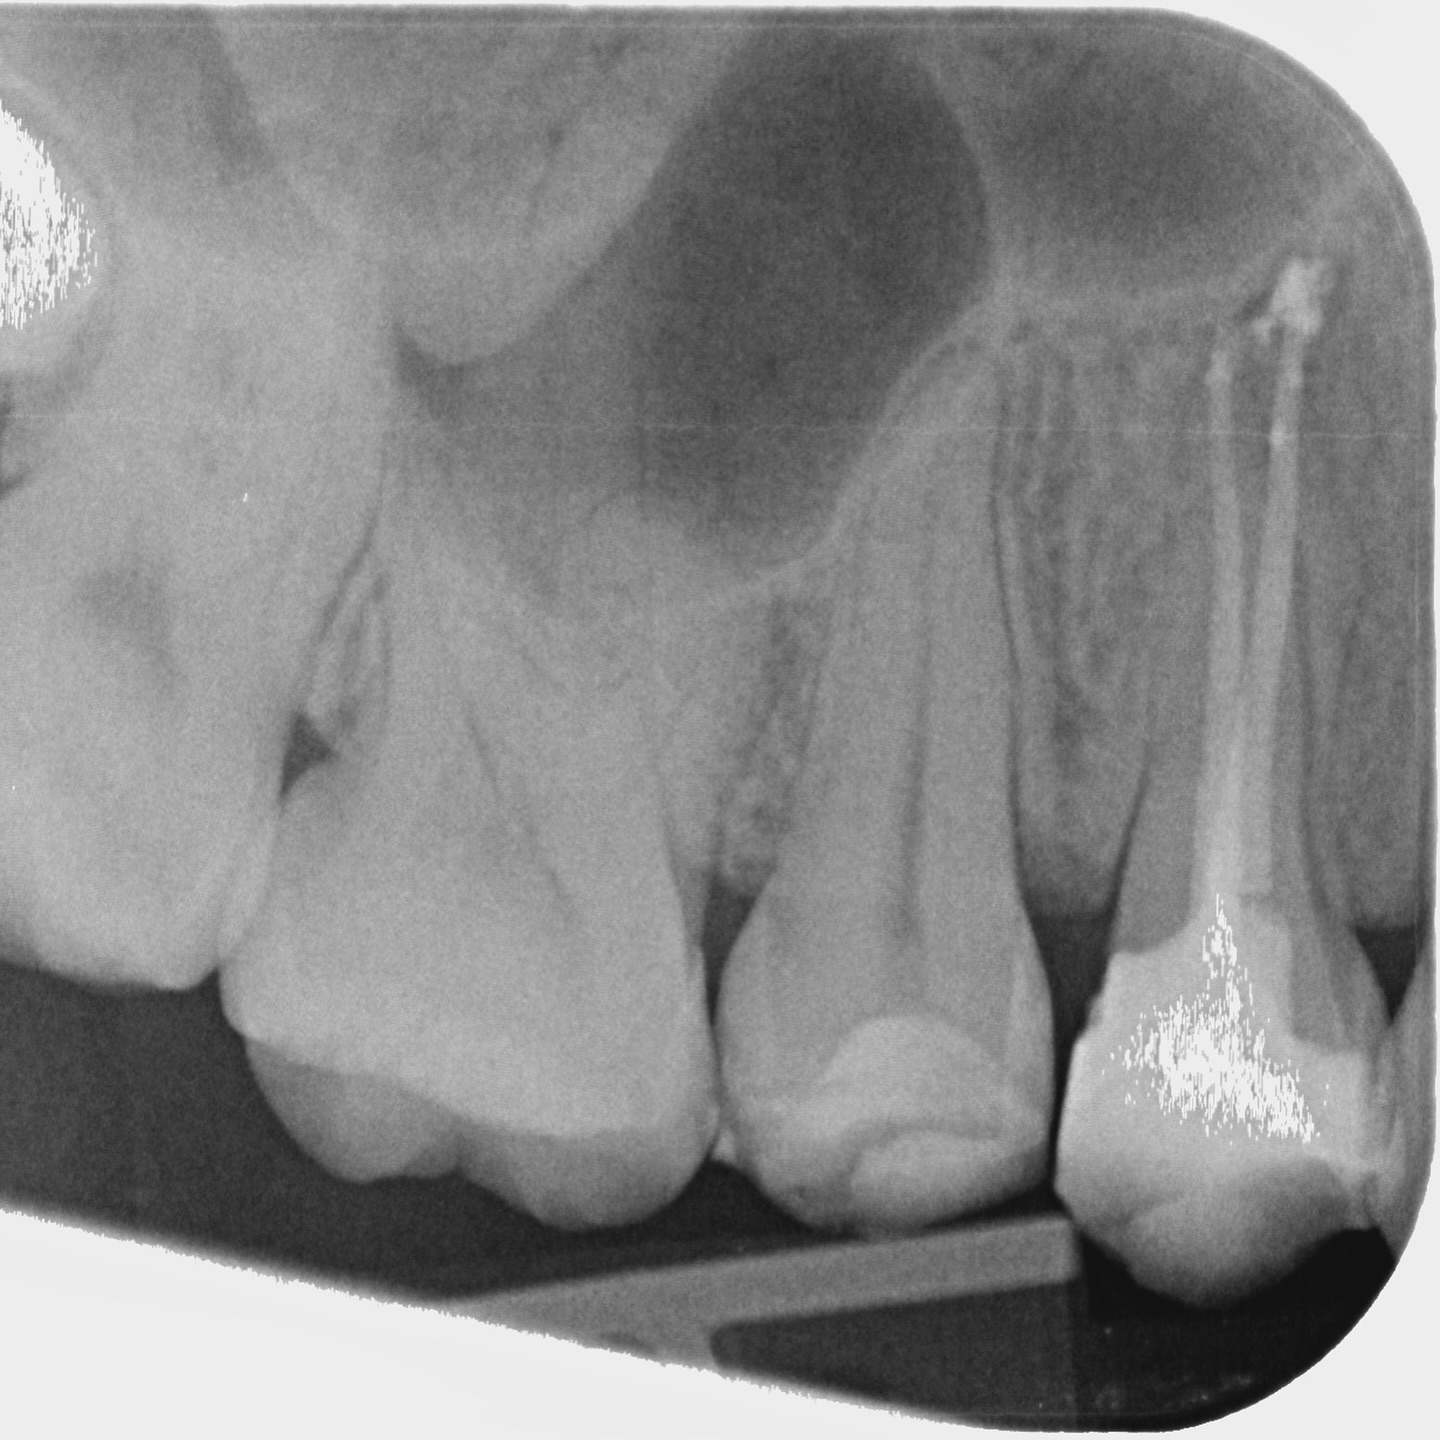

A comprehensive, non-specialist referral service for dental patients requiring affordable Endodontic treatment

Information regarding our services can be found here